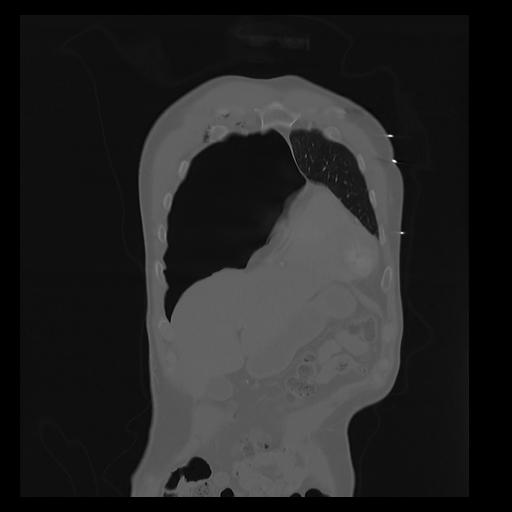

32 PULMON,CE,Coronal,3.000,PULMON,Coronal,